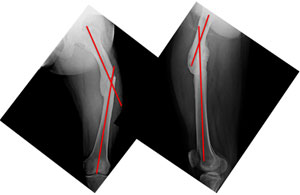

This 30 year old gentleman had met with an accident about 2 years back, following which there was a fracture of the left femur (thigh bone). He was treated at the local hospital where plating was done. The fracture healed and the plate was subsequently removed. He presented to us with deformity, shortening and awkward gait. The pictures here show the curvature in the thigh. The picture on the left shows an abnormal curvature of the thigh (red line) when we look from the front. The picture on the right shows the curvature of the thigh when we look from the side. Though it is a little proximal than normal, it is normal. |

| The x-rays at presentation showing the angulations of the femur at the fracture site. The picture on the left is as seen from the front with red lines showing the axes of the upper and lower segments. The angle between the two axes was about 34°, which should be 0° normally. The picture on the right is from the side and shows the angle between the axes (red Lines) to be about 20°, which is about 12-14° normally. |